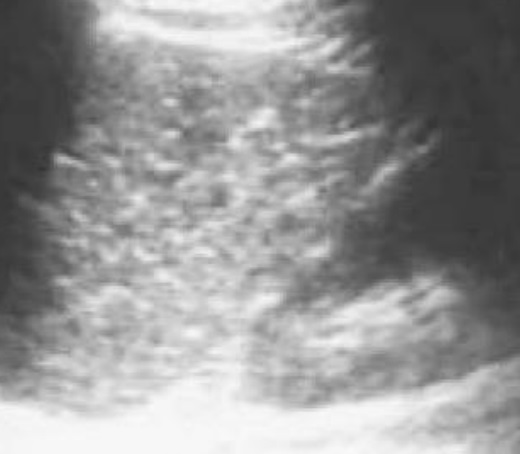

Aspect echographique de abces

fungique est multiple lesions hypoechogene arrodie

ou ovalaire a moindre 5mm diffuse dans le parenchyme

de la rate |